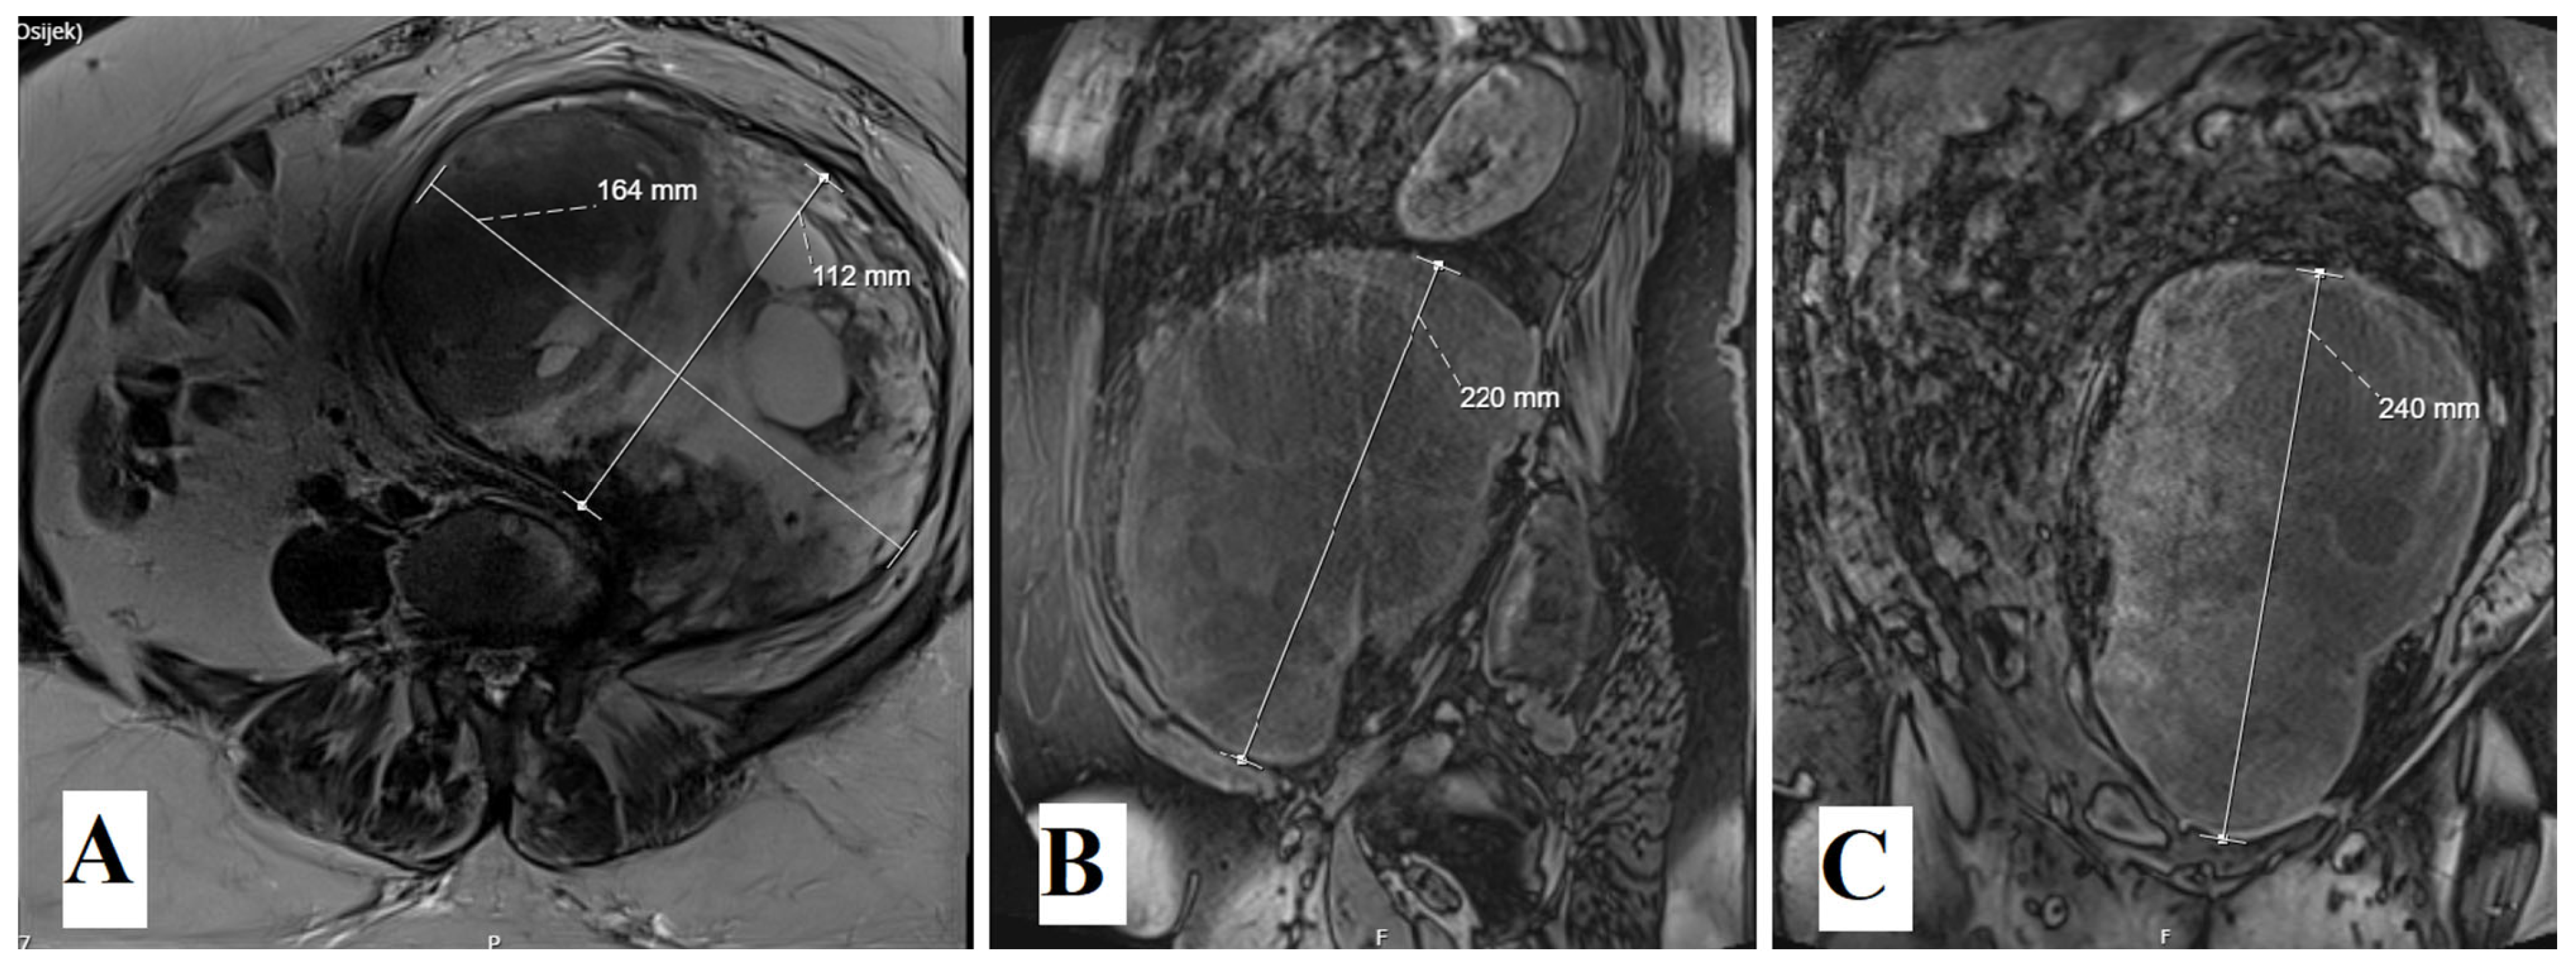

2. Case Report